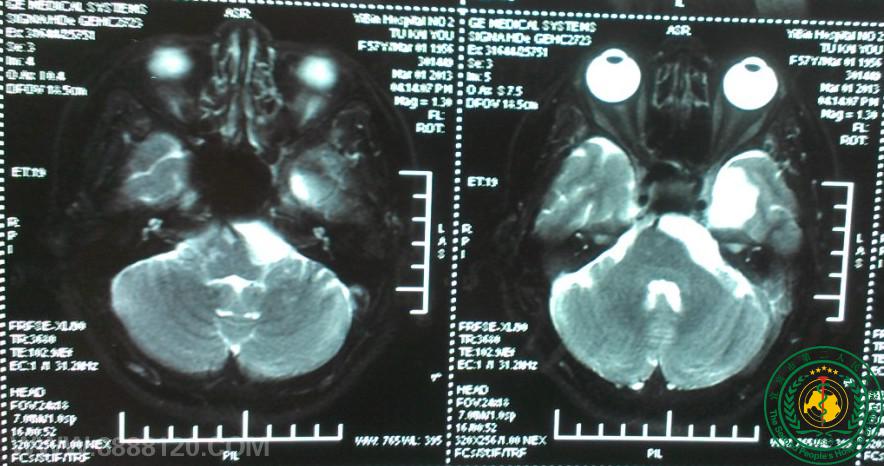

我科顺利完成颅内毗邻脑干肿瘤切除术一例

我科顺利完成颅内毗邻脑干肿瘤切除术一例5901